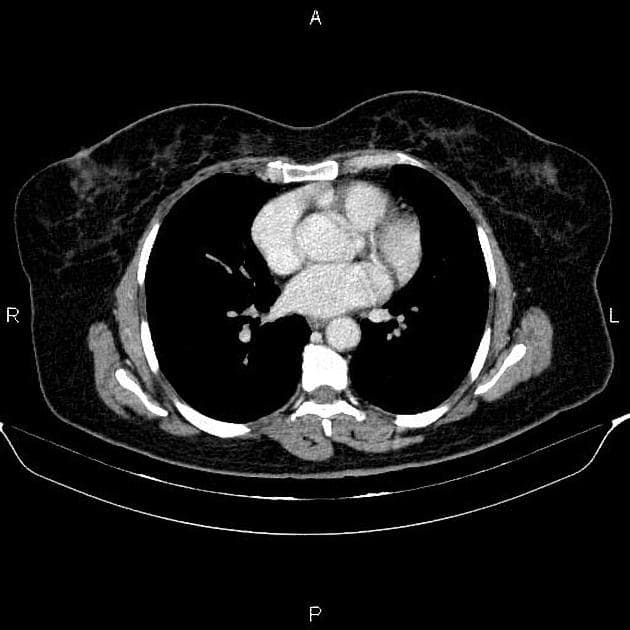

- Ngoài ra, phát hiện một tổn thương khối ở gan kích thước 10 x 12 mm ở thuỳ trái gan, phân đoạn II, có tín hiệu cao trên hình ảnh T2 trọng số nặng (heavily T2-weighted images). Tổn thương này cho thấy tăng quang ngoại vi và dạng nốt (peripheral and nodular enhancements), phù hợp với u mạch gan (Hepatic hemangioma). Một tổn thương tương tự khác kích thước khoảng 10 mm cũng được ghi nhận ở thuỳ phải gan, phân đoạn VIII.

- "Các phát hiện tình cờ lành tính như u mạch gan và nang vỏ thận là phổ biến và không nên nhầm lẫn với tổn thương di căn."

Trường hợp này biểu hiện ung thư cổ tử cung lan rộng tại chỗ với bằng chứng rõ ràng về xâm lấn parametrium và hạch chậu di căn, đáp ứng tiêu chuẩn giai đoạn IIIC1 theo hệ thống FIGO. Hạch vùng chậu trái có hạn chế khuếch tán và tăng quang sau tiêm thuốc, hỗ trợ chẩn đoán ác tính. Kết quả giải phẫu bệnh xác nhận ung thư biểu mô tế bào vảy kiểu sản sừng, dạng tổ chức học phổ biến nhất của ung thư cổ tử cung. Các tổn thương gan và thận lần lượt phù hợp với u mạch gan và nang vỏ thận đơn giản – đều là tổn thương lành tính, nhấn mạnh tầm quan trọng của việc định tính tổn thương chính xác để tránh phân giai đoạn quá mức. Việc phân giai đoạn chính xác định hướng điều trị, với giai đoạn IIIC1 thường được điều trị bằng hóa xạ trị thay vì phẫu thuật.